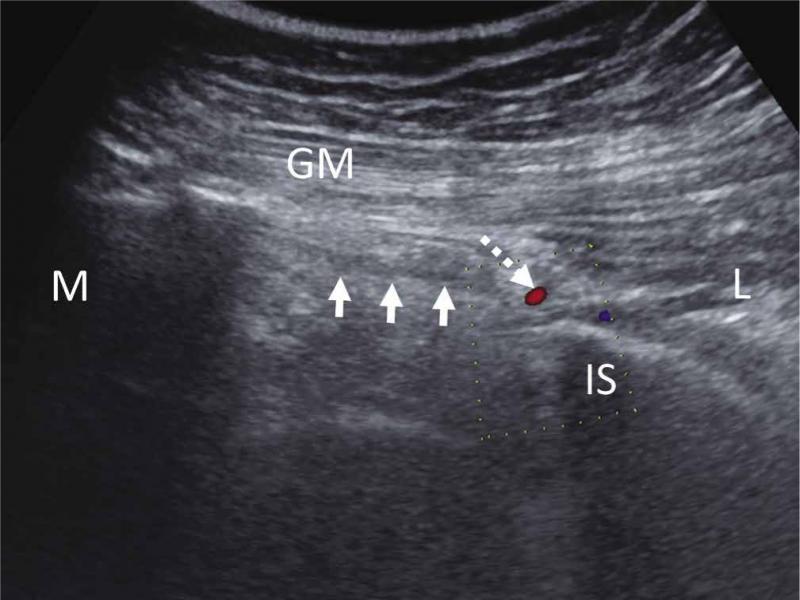

Fig. 4.